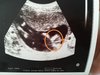

Dziewczyny, jak myślicie chłopczyk czy dziewczynka? ;) pytam z ciekawości ;)

Załączniki

• IMG_20190304_200806.jpg

IMG_20190304_200806.jpg

1,3 MB · Wyświetleń: 134